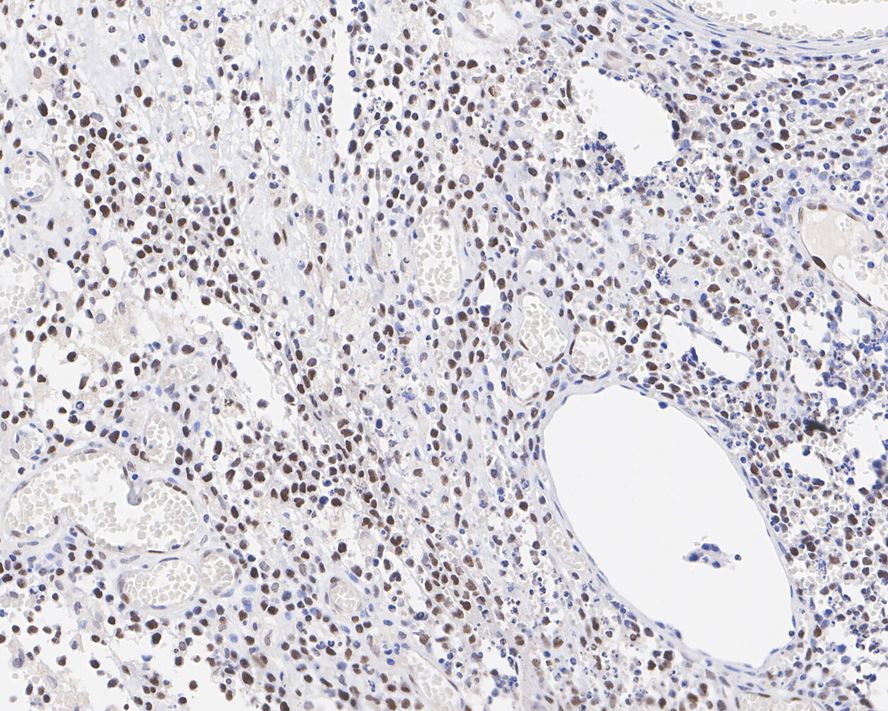

Immunohistochemical analysis of paraffin-embedded human breast cancer tissue with Rabbit anti-KMT6 / EZH2 antibody (ET1701-56) at 1/500 dilution.

The section was pre-treated using heat mediated antigen retrieval with Tris-EDTA buffer (pH 9.0) for 20 minutes. The tissues were blocked in 1% BSA for 20 minutes at room temperature, washed with ddH2O and PBS, and then probed with the primary antibody (ET1701-56) at 1/500 dilution for 1 hour at room temperature. The detection was performed using an HRP conjugated compact polymer system. DAB was used as the chromogen. Tissues were counterstained with hematoxylin and mounted with DPX.